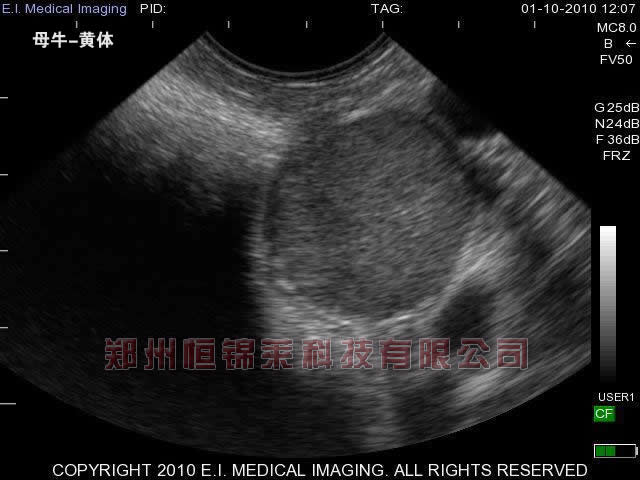

牛用B超观察牛初配年龄与配种时间